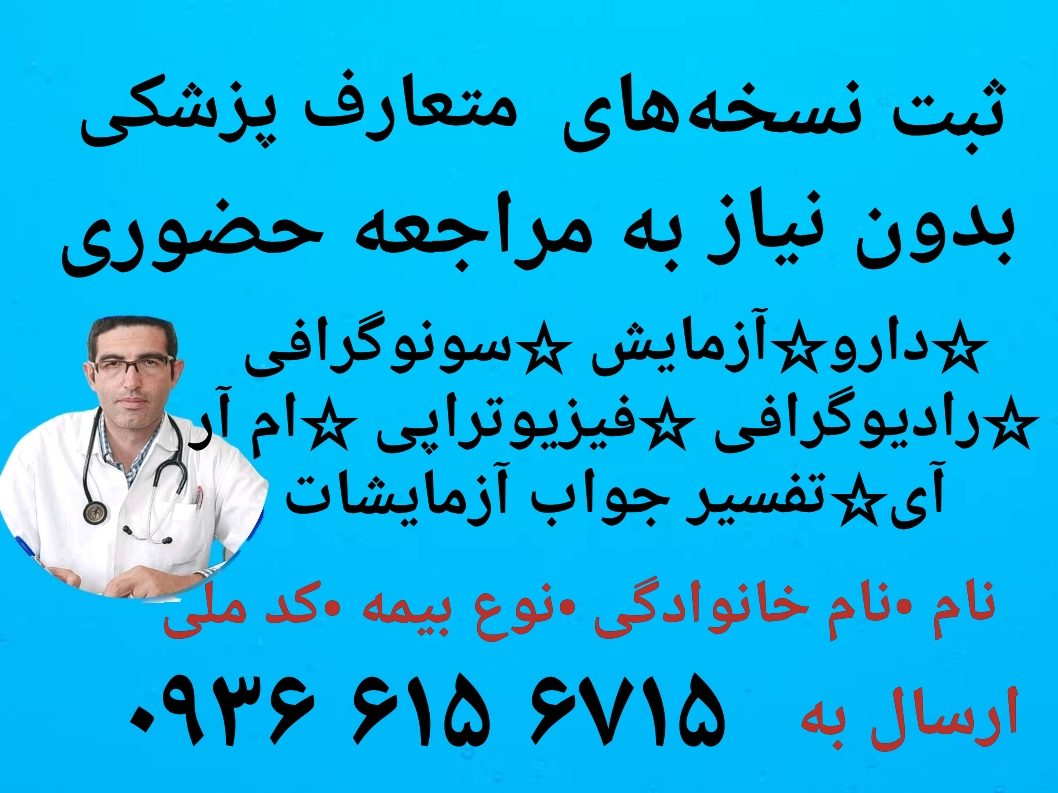

مشاوره آنلاین ارتوپدی با بهترین دکتر ارتوپد چرا مشاوره آنلاین ارتوپدی؟ چه بیماریهایی با مشاوره ارتوپدی آنلاین قابل بررسی هستند؟ مزایای دریافت مشاوره ارتوپدی غیرحضوری چگونه مشاوره آنلاین ارتوپدی دریافت